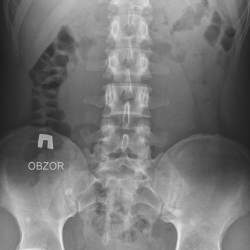

Женщина 60 лет. Оперирована справа. Аллергик, экскреторная урография не выполнялась. Слева на уровне L4 артефакт пленки. Обзорная цистография сделана отдельно - чисто.